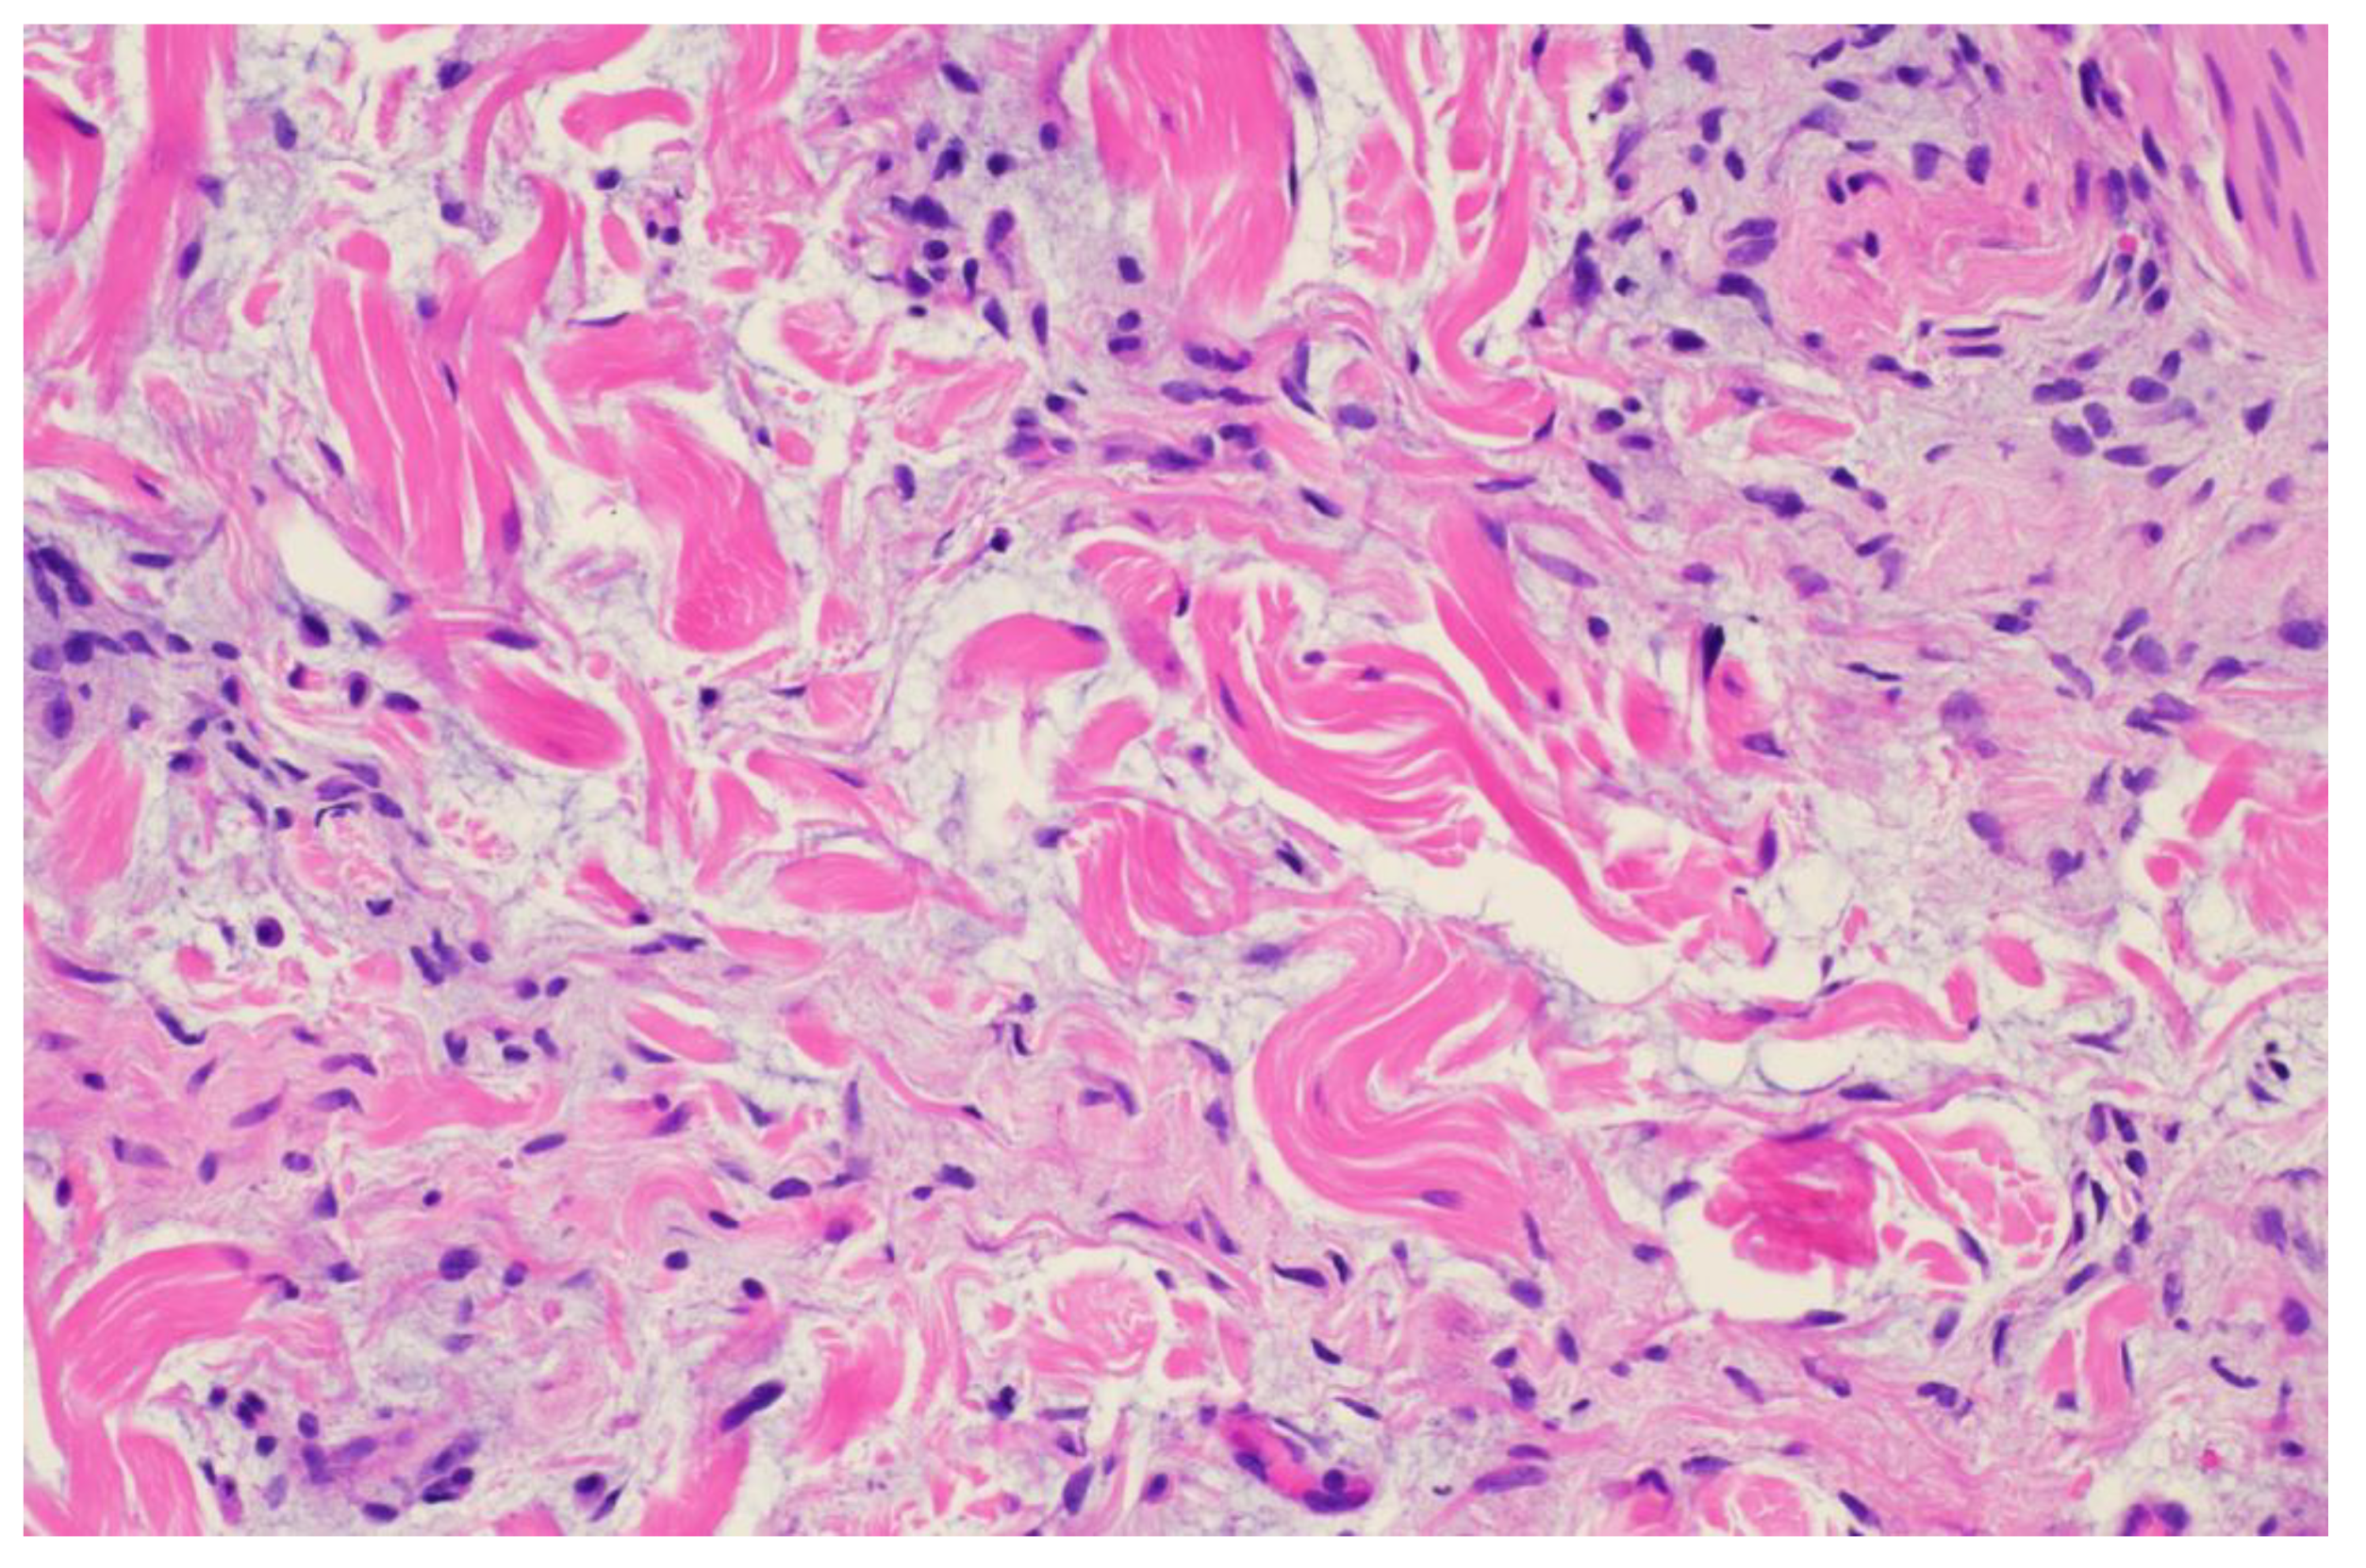

A 26-year-old male with a history of 0.4 mm malignant melanoma of the left upper extremity status post wide local excision and tenuous sun protection presented to clinic for follow-up. Exam revealed multiple scattered nevi to the head, trunk, extremities, feet, and genitalia as well as an erythematous plaque with central hyperpigmentation to the right upper arm in proximity to the shoulder (

Figure 1). A punch biopsy was obtained and revealed atypical myxoid spindle cell neoplasm and involved margins with overlying mildly atypical compound melanocytic nevus. The specimen also displayed CD34 positivity (histopathology displayed in

Figure 2,

Figure 3,

Figure 4,

Figure 5,

Figure 6,

Figure 7,

Figure 8 and

Figure 9). A diagnosis of spindle cell lipoma was reached, and wide local excision with 2 cm margins was performed and subsequent pathology revealed clear margins.

This case highlights an atypical presentation of spindle cell lipoma. The patient was a 26-year-old male with a history of malignant melanoma, who presented with an erythematous plaque on the right upper arm near the shoulder, an area that is not typically associated with SCL. Furthermore, the clinical presentation included central hyperpigmentation, which is not a common feature of SCL. The initial differential diagnosis was broad due to the atypical appearance of the lesion and CD34 positivity.

Histopathologically, the presence of an atypical myxoid spindle cell neoplasm with CD34 positivity further complicated the diagnosis. The biopsy also revealed an overlying mildly atypical compound melanocytic nevus, which is an unusual finding in SCL and raised concerns about a potential collision tumor or a misdiagnosis.